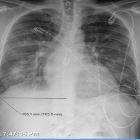

Dilated

cardiomyopathy secondary to chronic cocaine abuse: a case report. Chest X-ray- bilateral patchy opacities.